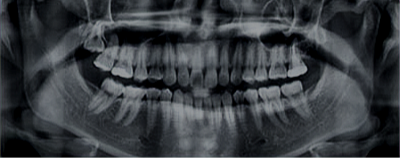

Radiografia Panorâmica

Descrição: Exame fundamental na odontologia por oferecer uma visão ampla das estruturas bucais e faciais em uma única imagem sendo utilizada em todas as especialidades.

Na Perfil Radiologia, realizamos esse exame com equipamentos modernos que garantem alta definição e baixa dose de radiação.

Visualização: ampla visualização dos ossos maxila e mandíbula, articulações temporomandibulares (ATM), seios maxilares, dentes e outras estruturas anatômicas importantes.

Utilização: todas as espcialidades para diversos tratamentos odontológicos,como ortodontia, implantodontia, extrações e avaliação de anomalias.